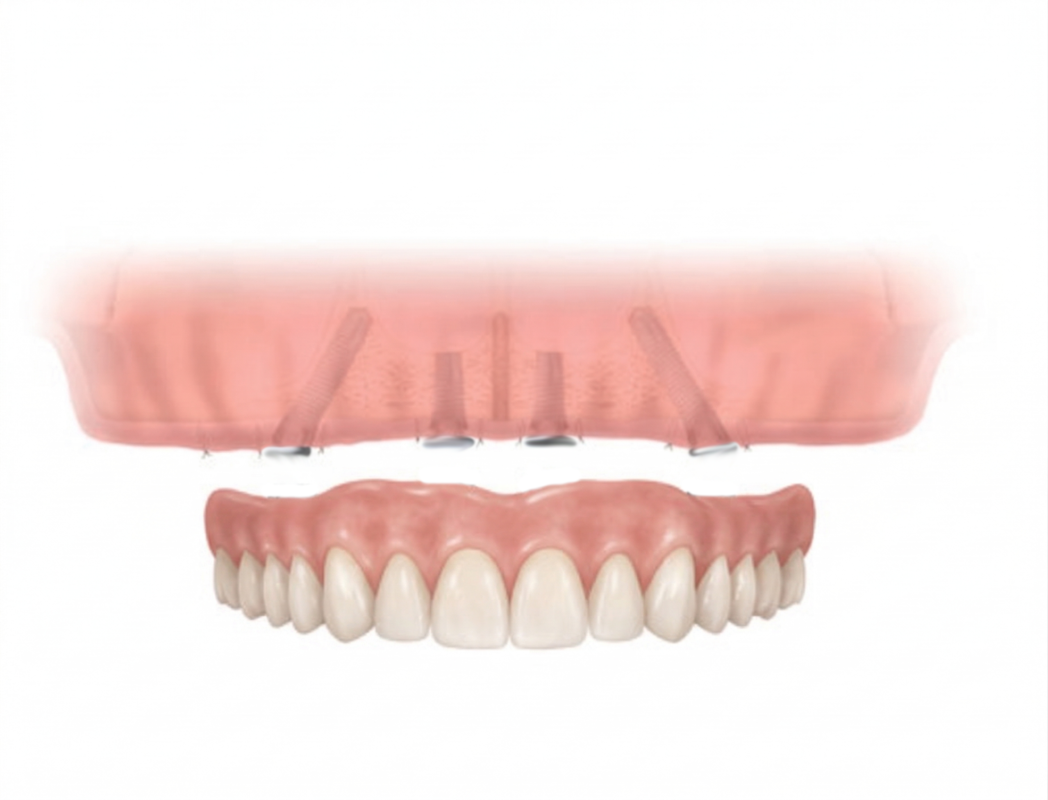

2. ProArch (All-on-4) Fixed Dentures

ProArch is Straumann’s treatment concept for immediate temporary restorations in edentulous patients. Whilst All-on-4 is Nobel Biocare’s tradename treatment concept for its immediate function fixed dentures. Straumann and Nobel Biocare are established global implant brands that has been manufacturing and producing implants for over 30 to 50 years*

The treatment concept is designed specifically for full-arch rehabilitation. And unlike traditional methods, this immediate concept combines the surgical and restorative phases into a single treatment phase period. Fixed provisional dentures are attached to the implants posts within days of the surgical surgery. By tilting the posterior implants, available dense bone typically in the anterior jaw is used to hold the implant post that often assists in eliminating the need for complex bone grafting at the posterior area. ProArch or All-on-4 is a solution option for patients with posterior bone loss.

For patients transitioning from failing natural teeth to a full-mouth restoration, ProArch and All-on-4 offers a quick 2 to 3 weeks treatment. After a healing period of approximately 6 months or more, the initial dentures is usually replaced with a longer-term set of denture.